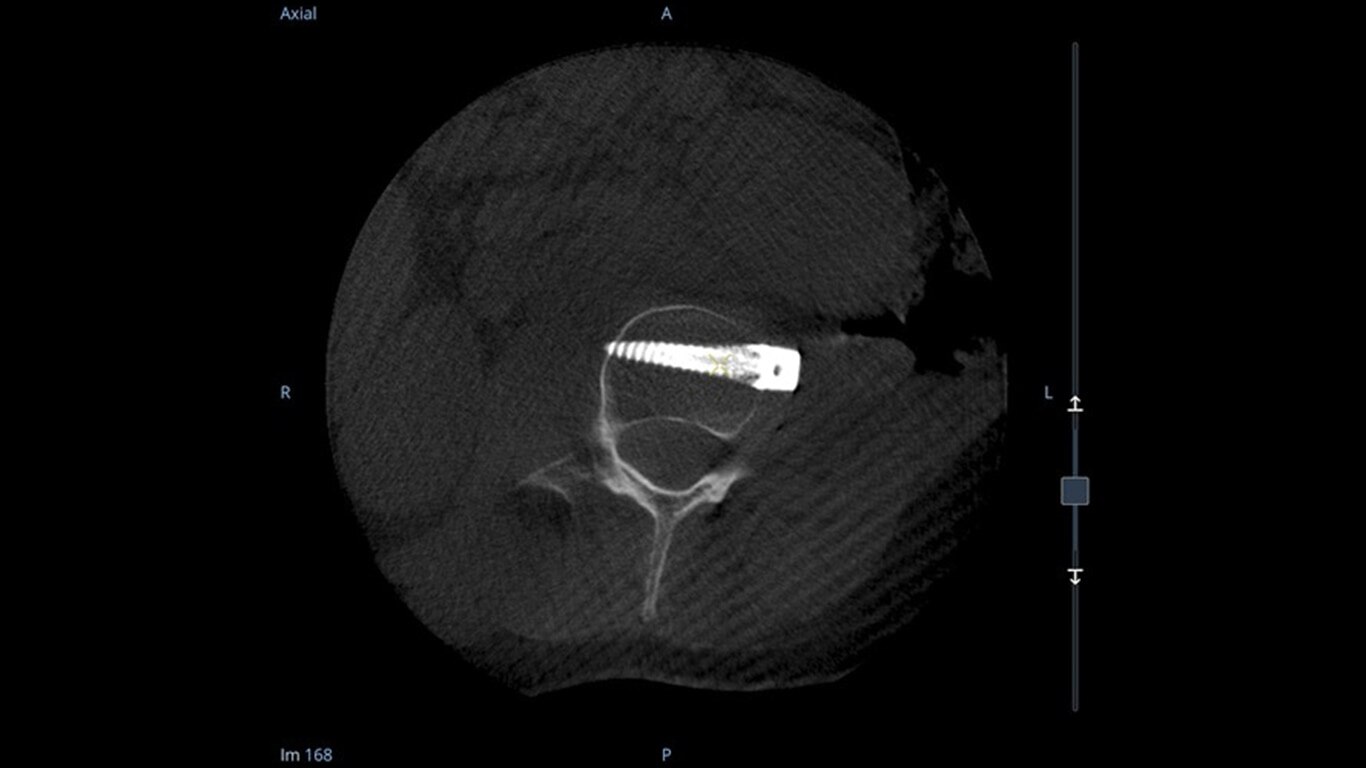

See more levels during a spinal fusion, or more of the pelvis or femur during an orthopedic procedure. With a 19 cm x 19 cm x 19 cm volume, OEC 3D captures a 67% greater volume than other 3D C-arms*.

Enhance intraoperative decision-making with visualization capabilities of Augmented Fluoroscopy in the OEC 3D Volume Viewer. Analyze five perspectives with 3D imaging tools including Multi-Oblique Mode, scrolling 512 slices, zoom, and more.